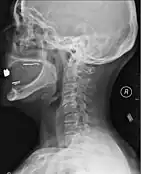

A radiographic evaluation using an X-ray, CT scan, or MRI can determine if there is damage to the spinal column and where it is located.[9] X-rays are commonly available[88] and can detect instability or misalignment of the spinal column, but do not give very detailed images and can miss injuries to the spinal cord or displacement of ligaments or disks that do not have accompanying spinal column damage.[9] Thus when X-ray findings are normal but SCI is still suspected due to pain or SCI symptoms, CT or MRI scans are used.[88] CT gives greater detail than X-rays, but exposes the patient to more radiation,[90] and it still does not give images of the spinal cord or ligaments; MRI shows body structures in the greatest detail.[9] Thus it is the standard for anyone who has neurological deficits found in SCI or is thought to have an unstable spinal column injury.[91]